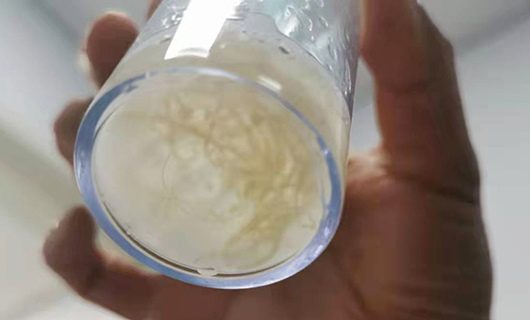

PART2:清除肺内塑型救患儿一命

29个月的贝贝(化名)来院时发热2天,喘憋1天,脸色发紫。医生听诊发现,贝贝左肺几乎没有呼吸音,肺CT检查发现左肺完全不张。内镜下,边鹏确诊贝贝为塑型性支气管炎,左肺已堵满。

边鹏说,塑型性支气管炎发病急、死亡率极高,如治疗不及时,可致进行性呼吸困难,危及生命;或经治疗后症状好转,但遗留坏死性肺炎、闭塞性支气管炎等严重后遗症,给患儿肺功能造成不可逆的损害。支气管镜治疗是有效的处置方法。经多次吸引灌洗后清除塑型,镜下给药,贝贝终于平安了。